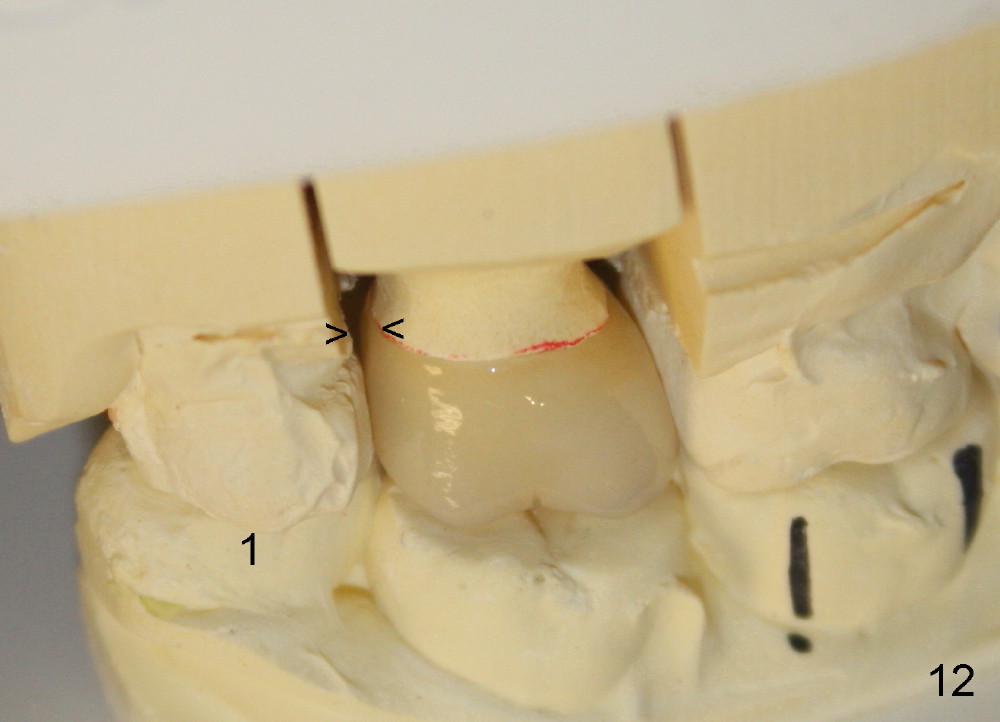

A 48-year-old lady is a dental phobic and has generalized chronic periodontitis. Bone loss around the tooth #2 has been severe for the last 5 years (Fig.1,2 *). Finally she agrees to have #2 (symptomatic) extracted and immediate implant placed (Fig.3 I). A 7x17 mm implant has to be used to achieve primary stability. The remaining buccal and lingual gaps are filled with allograft and membrane (Fig.4 *). Fig.5 shows that there is a space between the tooth #1 (asymptomatic) and the immediate implant (I). The wound/socket is protected by applying perio dressing around an abutment (Fig.6 A). Postop the patient is pain free; the perio dressing dislodges by itself. She returns 3.5 months later for restoration; but the tooth #1 has shifted mesially (Fig.6 arrow). The patient is not so willing to have #1 removed. Bands and bracket are placed in the neighboring teeth including a provisional crown to move the shifted tooth (with mobility) distally (Fig.7,9). The 2nd reason for #1 shifting is abnormal occlsual scheme on the right posterior region (Fig.8); mobility of #1 is the 1st one. The 3rd one is probably bruxism. In 5-6 weeks, the tooth #1 has moved to a desirable position (Fig.10, as compared to Fig.3,5). There is enough space for restoration (Fig.11,12).

In all, posterior immediate provisional should have normal proximal contact so that the neighboring periodontally affected teeth do not shift while the implant is osteointegrating. In order to avoid fibrointegration, the occlusal contact should be off. The patient requests an immediate provisional for the next implant. The same restoration will be fabricated for an implant at a healed site.